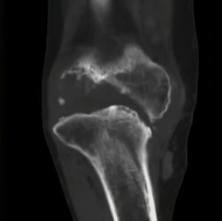

看上图这个病人,左膝是痛风性关节炎的患侧,右膝相对正常。左右膝对比就可以看出,左膝因为痛风性关节炎的影响,关节力线已经不好,即髋膝踝3点的连线不通过,膝关节,出现严重内翻膝的情况。而且关节间隙(圆圈处)已经不平衡,导致软骨磨损严重。且患者出现部分骨缺损情况,就是这个骨头没有了,无法承重了。

痛风性关节炎骨缺损